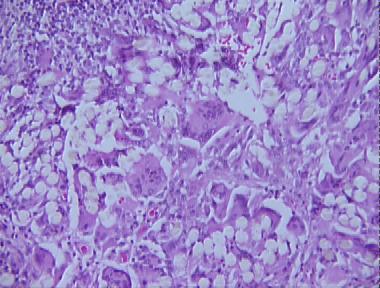

foreign body panniculitis

Histologic Features